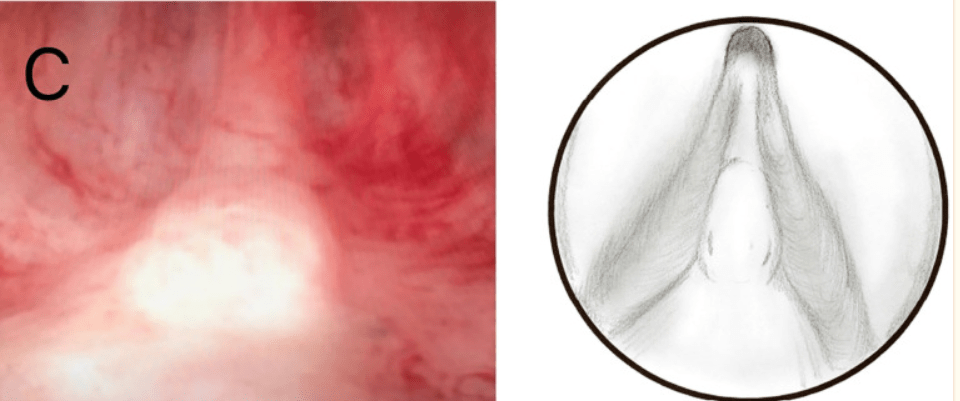

El Verumontanum también conocido como colículo seminal o utrículo prostático, es una estructura ubicada en el suelo de la uretra posterior, que marca el límite uretral entre el segmento membranoso y el segmento prostático. Durante las resecciones endoscópicas, representa un punto de referencia del esfínter estriado e, implícitamente, es el límite inferior de cualquier cirugía prostática segura. Por lo general, tiene una longitud de 15 a 17 mm y una altura de 3 mm, aunque hay numerosas variaciones tanto de forma como de tamaño. A ambos lados de la cresta o colículo uretral, los orificios de los conductos de los conductos eyaculatorios se abren y el orificio del utrículo prostático se puede encontrar en el borde superior.

Es un reparo anatómico muy importante utilizado por los urólogos para limitar la cirugía endoscópica de la próstata sea por resección, plasma, láser o vapor de agua.